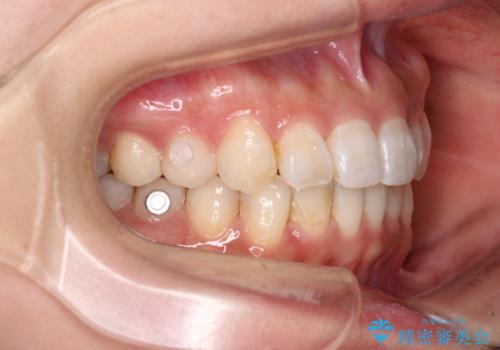

- 前歯のデコボコと深い咬み込みを気にして来院された患者様です。

インビザラインを用いて、前歯の叢生を解消するとともに、深い咬み合わせ(ディープバイト)を改善していくこととしました。

奥歯を後方に直立させることで深い咬み合わせを改善を図り、隠れていた下顎前歯が見えるほどになりました。